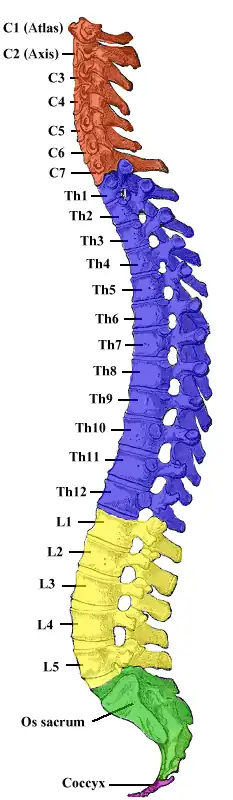

Als Lendenwirbelsäule (LWS) wird der in Höhe der Lende (lateinisch lumbo) gelegene, lumbale Teil der Wirbelsäule bezeichnet. Dieser Abschnitt besteht beim Menschen aus 5 Wirbeln, die als Lendenwirbel bezeichnet werden.

Beim Menschen wird die Lendenwirbelsäule durch den aufrechten Gang hoch belastet, sie stellt die Basis des Rumpfes dar. Durch diese Belastungen kommt es häufig zu schmerzhaften Reizzuständen. Der Oberbegriff „Kreuzschmerz“ mag dazu dienen, vom Schmerzsyndrom bis zum Bandscheibenschaden mit Ischialgien bzw. Lumbago oder auch neurologischen Ausfällen eine große Palette von Krankheitsbildern zusammenzufassen. Eine schwache Stützkraft im Lendenwirbelbereich kann sich bei Babys als Sitzkyphose zeigen. Form und Aussehen der Lendenwirbelsäule unterliegen beim Menschen einer großen Variabilität. Dies lässt die Annahme zu, dass die Anpassungen an die mit der entwicklungsgeschichtlich jungen Bipedie verbundenen aufrechten Körperhaltung in Stand und Gang womöglich noch nicht abgeschlossen sind.

Bei den meisten Säugetieren besteht die Lendenwirbelsäule aus sechs Wirbeln, bei Hunden und Katzen aus sieben. Die Wirbelzahl unterliegt allerdings einer gewissen Variabilität, so dass auch ein Wirbel mehr oder weniger auftreten kann.[1]